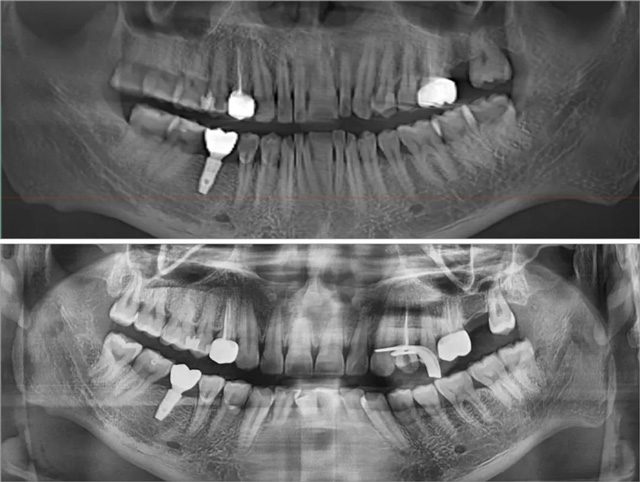

治疗前、治疗中全景片

经过拍片和口内检查,郭医生发现这颗牙已经是一个穿髓的状态,发展为牙髓炎了。由于龋坏深及牙髓,补牙材料与神经丰富的牙髓腔相通,刺激牙髓引发了疼痛。

“他这颗牙龋坏很深,补得也很深,可能因为材料刺激一直感觉不舒服,单纯补牙已经解决不了问题,需要做根管治疗。”

郭医生介绍说,目前,成年人的根管治疗基本全程无痛。躺上牙椅后先局部麻醉,再开髓、封失活剂,两周后清理牙根并放药,一周后再放入根充材料,根据需要考虑是否打桩,最后取模和安装牙冠。